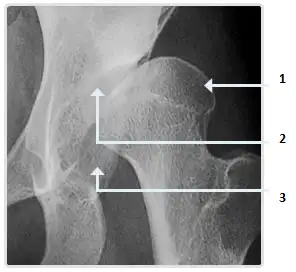

- Nẹp Chỉnh hình với chức năng NẮN CHỈNH lệch trục: để điều chỉnh, kiểm soát sự biến dạng, phát triển lệch trục. Bệnh nhân có các khớp biến dạng lệch trục sẽ dẫn đến các cấu trúc của dây chằng và bao khớp cũng như lớp sụn nhanh mòn hơn ở các khớp của người bình thường khác.